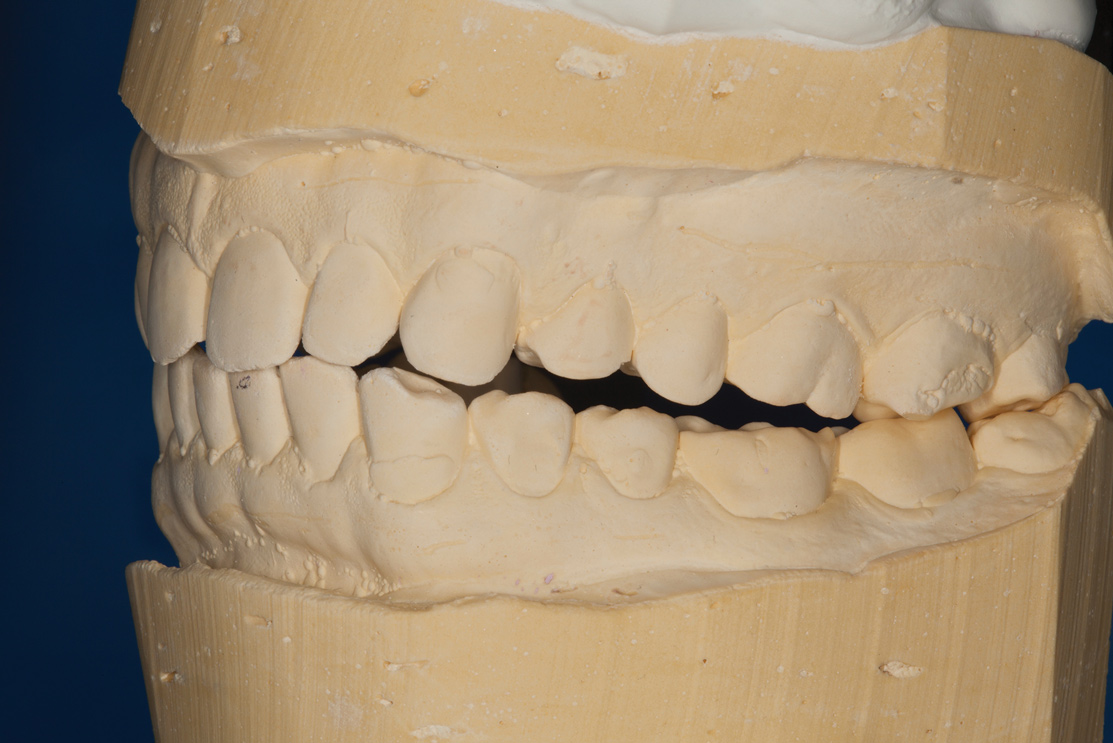

Confirmed by the mounted models (Figure 5), the patient's bite was obviously unsatisfactory, but with the orthotic in place, he was completely symptom-free and stable, and therefore, considered to be in acceptable function. However, he was considered to be in occlusal dysfunction without it because he lacked simultaneous, equal-intensity posterior contacts.

Fig 5. Mounted models showing maximum intercuspation.

Figure 5